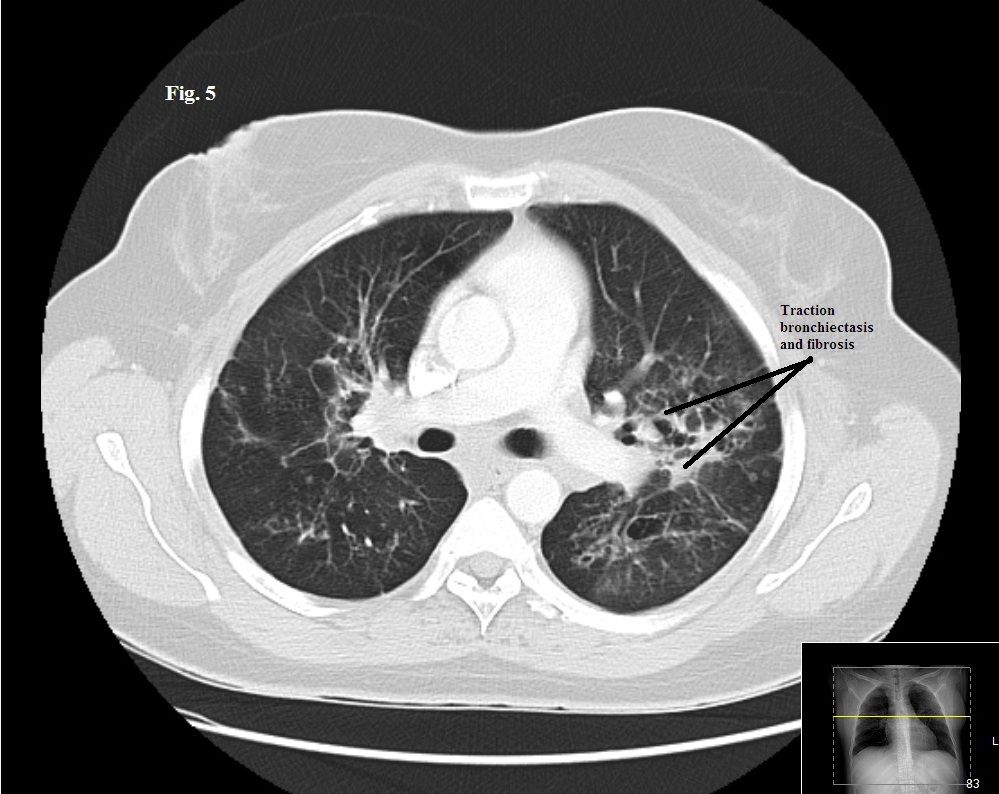

Figure 5. CT scan after 3 months of treatment.

Treatment with systemic prednisone was started at a dosage of 40 mg/d, and the patient’s symptoms improved significantly over 3 months. A repeated chest CT scan obtained at 3 months showed a mild decrease in the interstitial infiltrates and hilar lymphadenopathy (Figure 5). However, there was a prominence of traction bronchiectasis and cystic changes.